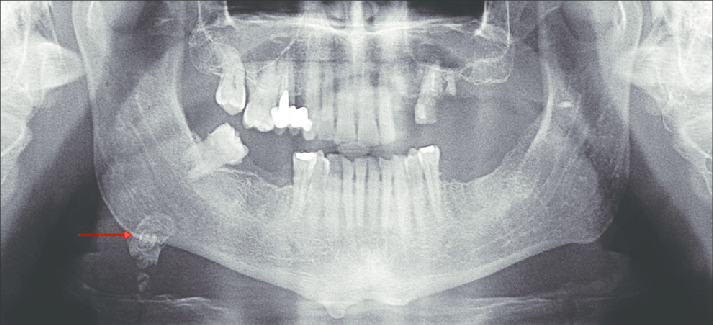

1. What condition can be seen in the following X ray? ( solid arrow)

the calcification within Stensen's duct of parotid